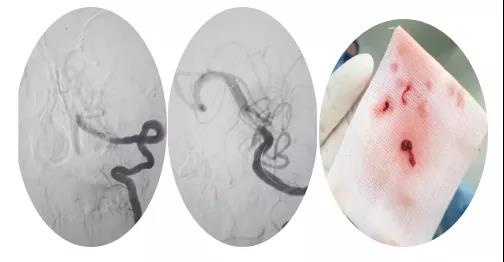

18:30手術(shù)開(kāi)始,造影為基底動(dòng)脈閉塞,與患者家屬充分溝通,患者家屬同意給予介入取栓治療。共取栓2次,取出少量暗紅色血栓塊。造影示:基底動(dòng)脈有重度狹窄,結(jié)合患者病情演變及造影結(jié)果,考慮為動(dòng)脈粥樣硬化性狹窄。根據(jù)患者造影結(jié)果,目前單純?nèi)∷o(wú)法達(dá)到預(yù)期效果,決定給予基底動(dòng)脈支架植入術(shù)。根據(jù)患者基底動(dòng)脈直徑選擇3.0*13mm apollo球擴(kuò)支架,支架植入后造影示狹窄消失。

支架植入后患者神志轉(zhuǎn)清,四肢均可活動(dòng),左側(cè)肢體活動(dòng)略差于右側(cè),收入神經(jīng)內(nèi)四科病房進(jìn)一步治療。術(shù)后第三天患者神志清,四肢活動(dòng)基本正常,住院5天轉(zhuǎn)入當(dāng)?shù)蒯t(yī)院治療。?